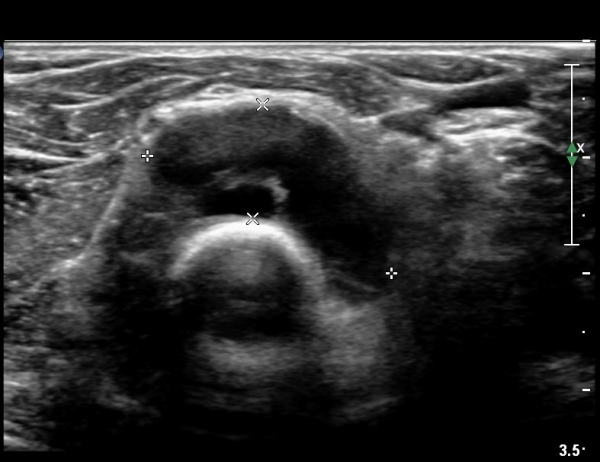

¿ä°ñµÎ ºÎÀ§ ÆÈ²ÞÄ¡ ¾Õ, ¿ÜÃø Ⱦ´Ü¸é°Ë»ç¿¡¼­ Èİñ°£ ½Å°æ ³»Ãø, ¿ä°ñµÎ Ç¥Ãþ¿¡¼­

ÀÛÀº ³¶Á¾ÀÌ °üÂûµÈ´Ù(»çÁø 3)

ŽÃÊÀÚ¸¦¸»´ÜÀ¸·Î  À̵¿ÇÏ´Ï ¿ä°ñ¸ñ ºÎÀ§¿¡¼­ Ä¿´Ù¶õ ³¶Á¾ÀÌ Èİñ°£ ½Å°æÀ» ¾Ð¹ÚÇÏ´Â °ÍÀÌ

°üÂûµÈ´Ù(»çÁø 4, 5)